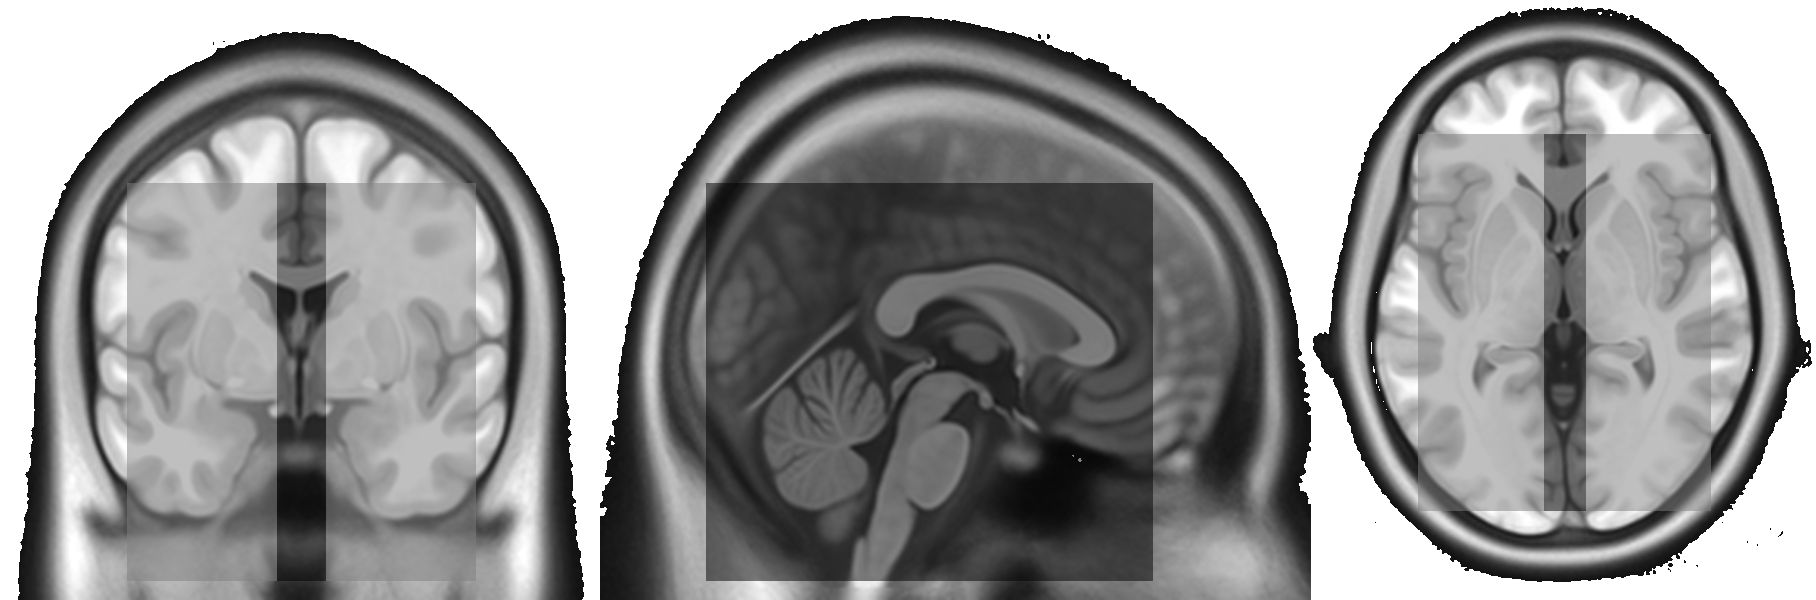

Refer to caption

Figure 4: Coronal (left), sagittal (middle), and axial slice (right) of the 128x128x128 voxel patches resulting from the optimized patch positioning. For reference, the T1 template of CAT12, upsampled to the utilized resolution of 0.5mm, is shown in the background.

Before applying patches from the right hemisphere to the UNet, we apply flipping along the sagittal axis such that they resemble left hemisphere patches. The resulting prediction is then flipped back. This approach reduces the number of effective patch positions individual UNets need to be trained for from 27 to 18.

Close to the border of a patch, the accuracy of the prediction typically decreases. Therefore, predictions close to the border of a patch are weighted less via Gaussian importance weighting [23] during accumulation of the final prediction containing 336x384x336 voxels.